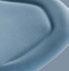

Figura 22. Caso clínico tratado mediante injerto óseo de lámina autóloga. Continuación. A) Reconstrucción volumétrica del área a intervenir antes del primer procedimiento quirúrgico. B) Reconstrucción volumétrica del área intervenida 4 meses después del primer procedimiento quirúrgico. C) Reconstrucción volumétrica de la zona de la rama mandibular de la que se obtuvo el injerto óseo autólogo, inmediatamente después de su obtención. D) Vista oclusal del área a reconstruir, antes del primer procedimiento quirúrgico. E) Vista oclusal del área reconstruida, 4 meses después del primer procedimiento quirúrgico. F) Vista transversal del área a reconstruir, antes del primer procedimiento quirúrgico. G) Vista transversal del área reconstruida, 4 meses después del primer procedimiento quirúrgico. H) Vista transversal de la zona de obtención del injerto óseo autólogo.

Figura 28. Caso clínico tratado mediante injerto óseo de lámina alogénica (Cortical Plate Salugraft®). A) Situación clinical basal. B) Situación radiográfica (3D) basal en posición de 45. C) Situación radiográfica (3D) basal en posición de 46. D) Extracción de 45 y elevación del colgajo a espesor total. E) Fijación de las láminas alogénicas (Cortical Plate Salugraft®) vestibular y oclusal.

Figura 30. Caso clínico tratado mediante injerto óseo de lámina alogénica. Continuación. A) Vista vestibular tras 4 meses de cicatrización. B) Vista oclusal tras 4 meses de cicatrización.

C) Vista transversal radiográfica (3D) en posición de 44. D)

Vista transversal radiográfica (3D) en posición de 45. E) Vista transversal radiográfica (3D) en posición de 46. F) Reentrada tras 4 meses del procedimiento quirúrgico.